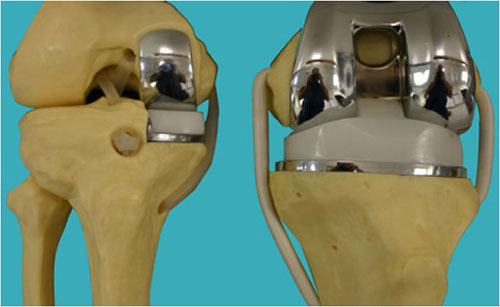

Trong phẫu thuật thay thế toàn bộ khớp gối, hai đầu của đùi bị tổn thương và xương chân dưới (ống chân) và đôi khi xương bánh chè được phủ bằng bề mặt nhân tạo. Những bề mặt này được làm bằng kim loại và nhựa. Nhựa hoạt động như sụn cứng, giúp khớp của bạn di chuyển tự do. Các bộ phận kim loại và nhựa của khớp nhân tạo cho phép đầu gối của bạn uốn cong trong khi cũng làm cho nó ổn định hơn. Trong hầu hết các trường hợp, bác sĩ phẫu thuật thay thế toàn bộ bề mặt ở hai đầu đùi và xương chân dưới. Bác sĩ phẫu thuật thường bảo đảm các thành phần khớp gối vào xương bằng xi măng.